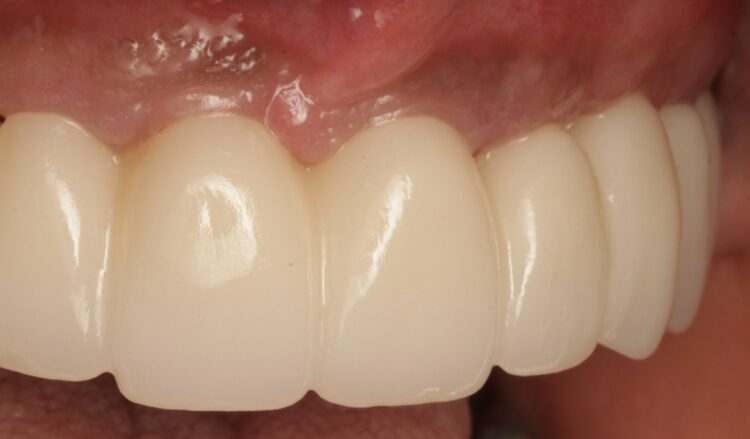

After four months, an IOS impression was executed and a digital dataset created superimposing the soft tissue, implant scan bodies, antagonist and temporary prosthesis scanning files. To avoid any inaccuracy in scalloped interface reproduction due to quick collapse of the gingival tissue, the provisional prosthesis was scanned both intraorally and extraorally, capturing its overall contour and, in particular, the transmucosal surface at the pontic sites and emerging profiles.

A titanium substructure was digitally designed (Bridge Base by Atlantis) taking into consideration the functional and aesthetic virtual wax-up and emergence profile as the FP1 provisional prosthesis shaped it. This metal substructure was anatomically shaped at the gingival and occlusal sides in order to tightly adhere at the soft tissue interface leaving at least 2mm of clearance for the zirconia superstructure.

Based on the digital design and copying the approved provisional prosthesis, a zirconia overlay was milled. The overlaying zirconia superstructure was digitally designed to fit the metal substructure, accomplish a flawless finish line, avoid any undercuts and verify the path of insertion, thus facilitating the bonding procedures. The zirconia superstructure was bonded with the titanium substructure using a self-curing luting composite. The final polished screw-retained prosthesis was delivered and torqued to 30Ncm and the radiographic assessment was executed.

After the follow up appointments at one and four weeks, the patient was scheduled for periodic maintenance every three months. The retrievability of the final screw-retained zirconia-titanium supported prosthesis allowed management of the interface over time. At the one-year review, further growth and maturation of the soft tissue as well as the health of the keratinised peri-implant tissues were evident, without signs of bleeding on probing.